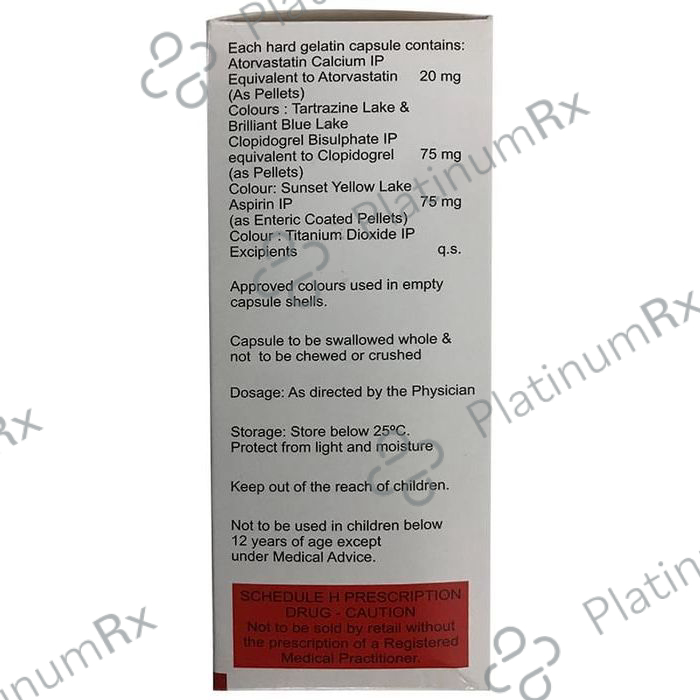

Aspirin 75mg + Atorvastatin 20mg + Clopidogrel 75mg

Salt CompositionAspirin 75mg + Atorvastatin 20mg + Clopidogrel 75mg (same for both)

Atorva Gold 20/75/75mg Capsule 15s

Atorva Gold 20/75/75mg Capsule 15s

Zydus Cadila

₹141.1